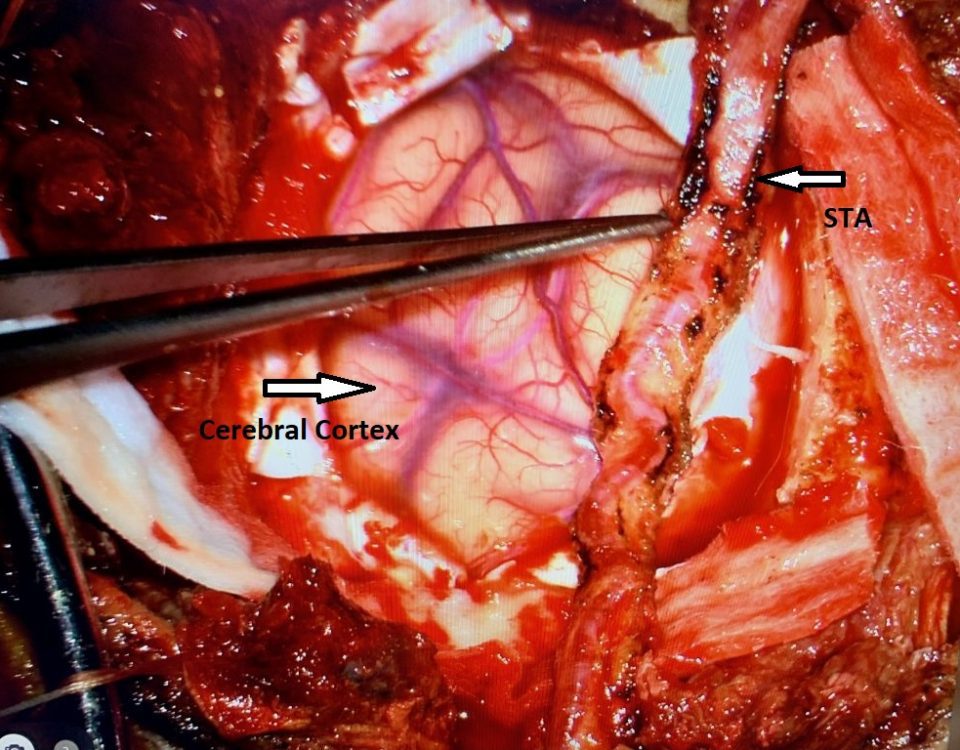

MRI with gadolinium confirmed the likely diagnosis of convexity meningioma, a benign neoplasm of the meninges. Given the location of the tumor, angiography and embolization were […]